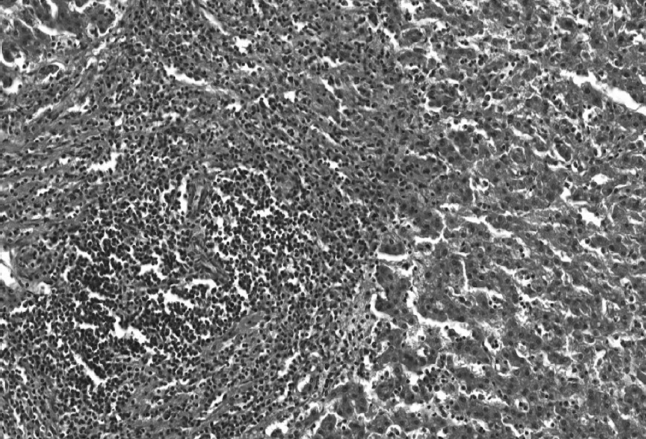

Во всех исследуемых случаях на фоне выраженных дистрофических изменений в ткани печени отмечались разной степени выраженности склеротические изменения стромы: от разрастания рыхлой, нежноволокнистой соединительной ткани вокруг центральных вен с незначительным расширением портальных трактов до выраженного перипортального и центролобулярного перивенулярного фиброза, а также местами перицеллюлярного фиброза. В 19 % исследуемых случаев (18 женщин, 11 мужчин) в ткани печени мы наблюдали выраженную перестройку структуры ткани печени вследствие формирования портального цирроза печени. В исследуемых образцах ткани печени отмечалось вклинение в печеночные дольки тонких фиброзных септ из расширенных фиброзированных перипортальных полей с последующим соединением центральных вен с сосудами портальных трактов и образованием мелких ложных долек, состоящих из пролиферирующих гепатоцитов в состоянии жировой и белковой дистрофии с отсутствием радиальной ориентации печеночных балок (рис. 3).

Рис. 3. Цирроз печени с формированием ложных долек, состоящих из гепатоцитов в состоянии выраженной жировой и белковой дистрофии (окраска гематоксилином и эозином, ув. ×100)